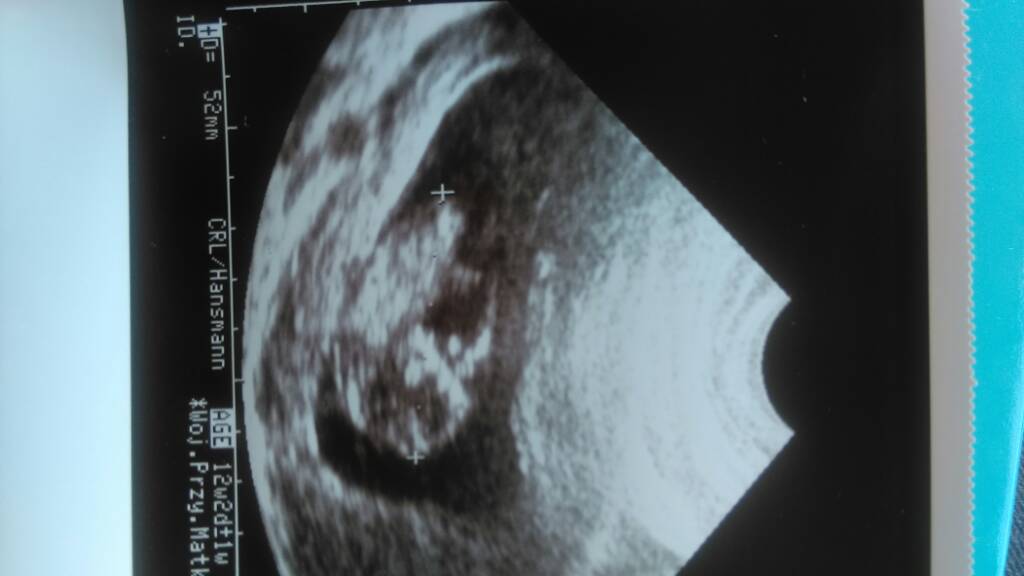

Hej kobietki [emoji8] Ja już po wizycie. Badania z krwi wyszły elegancko. Fasola rośnie ma 5,2cm. A dopiero co niedawno było 2,5...Powiedźcie mi czy Wam też z każdym usg zmienia się termin rozwiązania? Najpierw miałam 12.01, później 11.01, a dziś wyszło, że 07.01. Jak to jest? Następna wizyta 18 lipca. A pojutrze prenatalne [emoji4] Buziaki [emoji8]